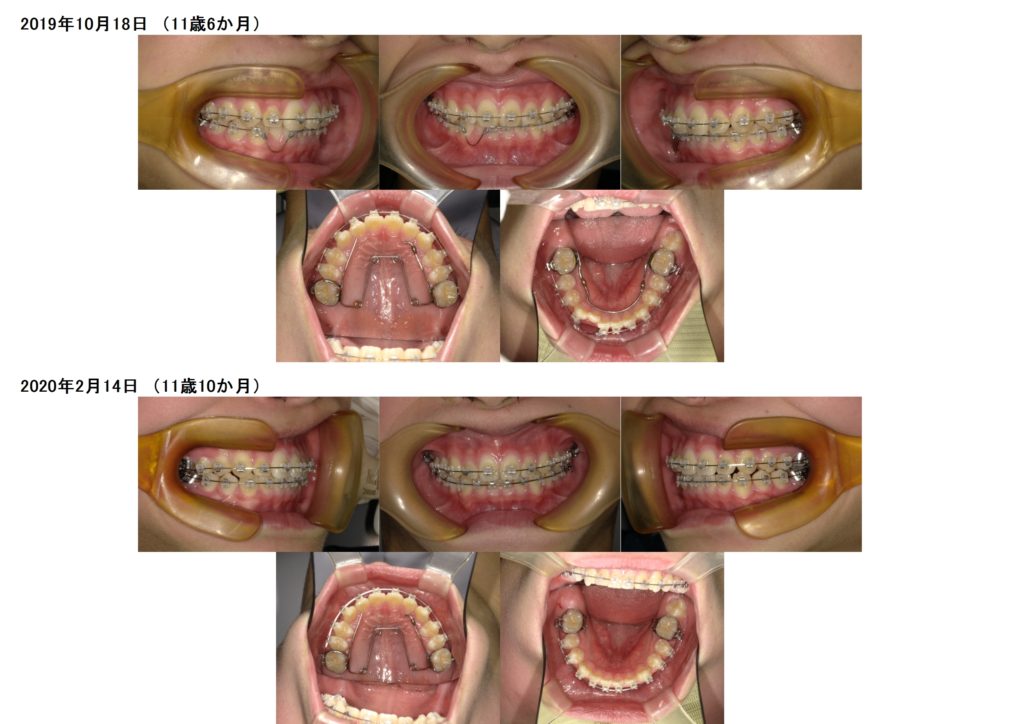

↑調整を繰り返し、、、、

↑ジャ~ン!!外れました!!